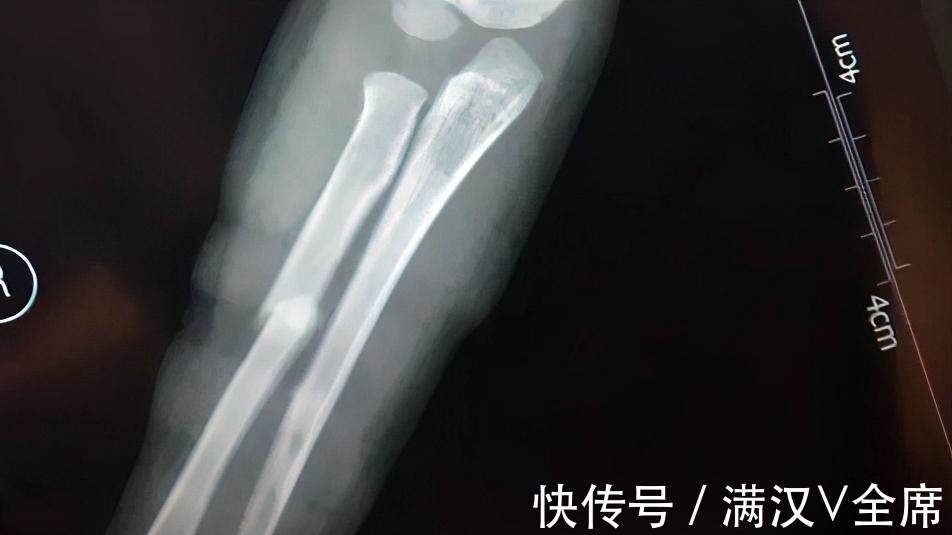

滑梯|5岁孩子“逆行”上滑梯,被迎面滑下的大孩子推倒摔骨折,竟被指家长没教育好

【 滑梯|5岁孩子“逆行”上滑梯,被迎面滑下的大孩子推倒摔骨折,竟被指家长没教育好】一个5岁的孩子,自下而上往滑梯上爬,结果被上面滑下来的大孩子一把推倒,摔出滑梯,造成骨折。当这样的事情发生,该受指责的是谁?

那是一处设置在商场内的儿童滑梯,这个5岁孩子受伤时,家长就在旁边,只是没看到具体情况。事后细想,觉得事情有蹊跷,去调取了监控才发现,孩子是被人从正面直接推倒,摔下滑梯后受伤的。